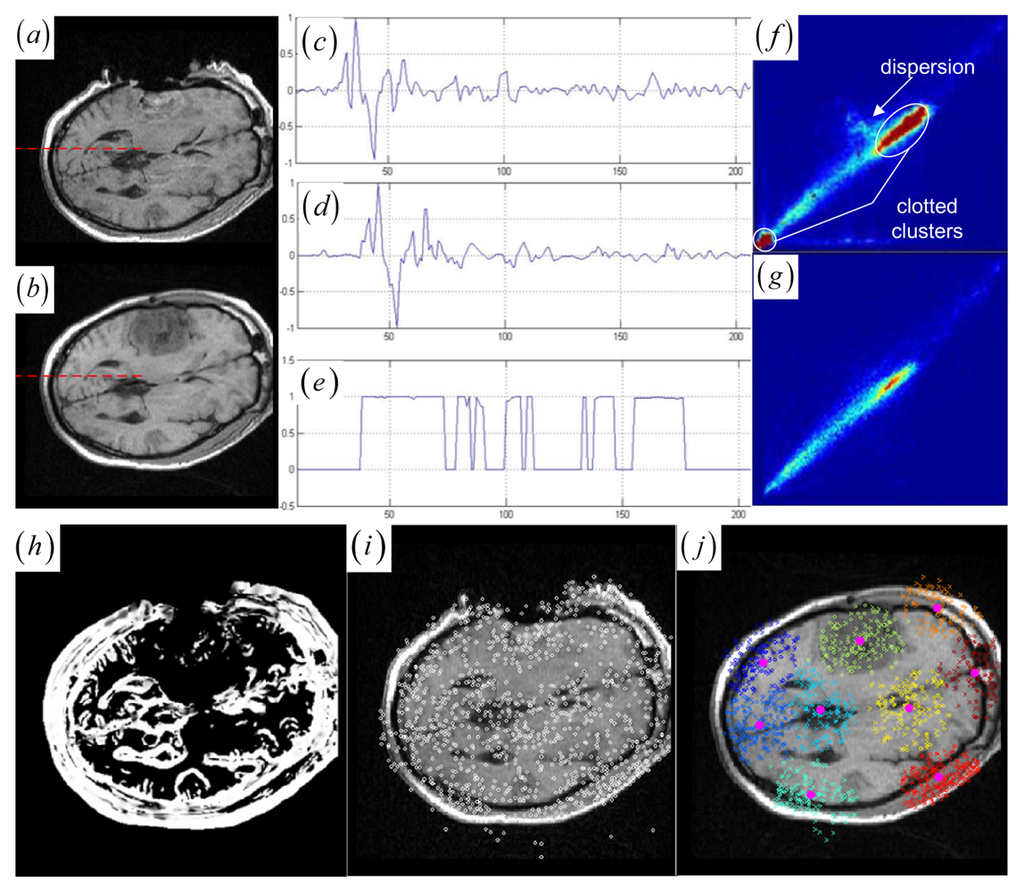

Note that if one cluster pair of tumor regions suffers from the large structural mismatches with local large deformation and outliers, this cluster pair will bring together many keypoints and small average JSM value ζk (computed as ζk = Σw (yi)/card (Ck) (yiCk)). Therefore, the keypoint cluster of tumor region in each image can be localized if its ζk is below a threshold value (ζthreshold = 0.4). In Figure 1j and Figure 2a,b, the keypoint clusters in both images are sorted according to the average JSM values {0.266, 0.404, 0.494, 0.533, 0.560, 0.565, 0.590, 0.639, 0.734}. The tumor resection clusters with ζ1 = 0.266 could be automatically detected from the nine clusters. Figure 2e,f shows that the two images have ten clusters with the tumor resection cluster having 0.234 average JSM value. Furthermore, the keypoint clusters of tumor regions in both images could be regarded as an ellipse model based on the mean and variation of the cluster, and then the outlier keypoints inside the ellipse are removed while the boundary significant keypoints (Figure 2c,d,g,h) are saved for subsequent correspondence detection, i.e., delete x = (x, y) if [ (xμx)2/(κσx)2 + (yμy)2/(κσy)2] < 1 with κ = 0.1. After outlier keypoint rejection, we approach the control point setup and related correspondence detection as follows.

• Choose the significant keypoints for irregular control point setup. The SIFT keypoint detector has assigned a location and a scale to each stable DoG keypoint. The scale defines the saliency measure of each keypoint such that the keypoint with a large scale could be identified at the same location in the noisy pre- and intra-operative MR brain images. Based on the above consideration, a keypoint with the largest scale measure within a neighborhood could be saved as the significant keypoint in a cluster. In Figure 2a,b,e,f, the significant keypoints selected from each cluster well represent the irregular control point setup in the salient structures. Figure 2c,d,g,h shows the boundary significant keypoints at the tumor resection clusters.

Figure 2. (a)–(b) and (e)–(f) Clustered significant keypoints in the two images. (c)–(d) and (g)–(h) Boundary significant keypoints around tumor resection regions with circles defining the scale measures of the points.